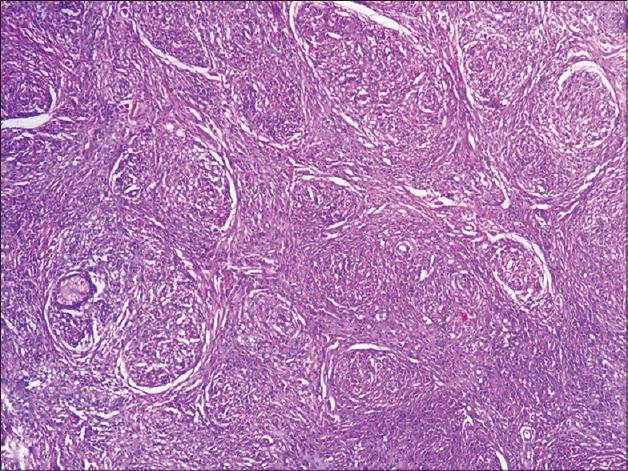

Molluscuoid lesions over the body.

A clinical and histopathological study of histoid leprosy.组织样麻风的临床和组织病理学研究。

THE HISTOID VARIETY OF LEPROMATOUS LEPROSY.

Status of histoid leprosy--a clinical, bacteriological, histopathological and immunological appraisal.